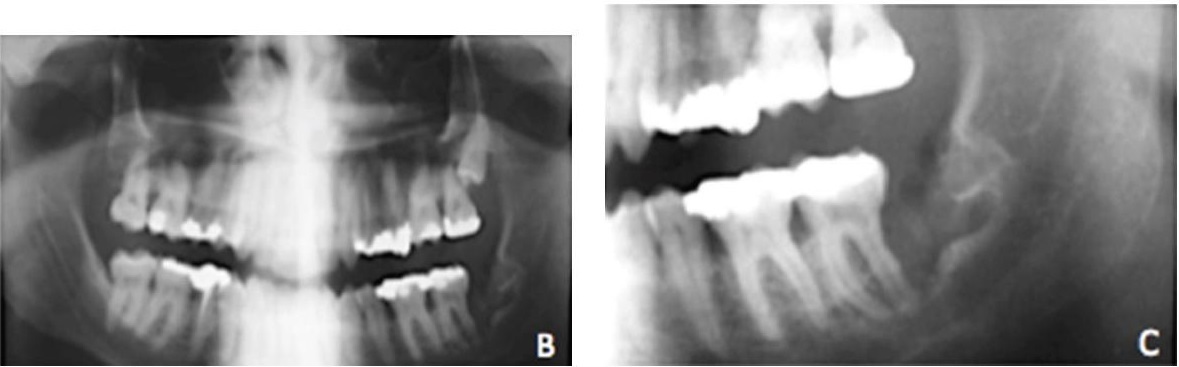

Изначально заболевание прогрессирует без какой-либо симптоматики, и выявить проблему в этот период возможно лишь на рентгенограмме. Если вовремя обнаружена киста на десне, лечение поможет сохранить зуб. В сильно запущенных случаях единственный выход - удаление.

Киста на десне: фото до и после